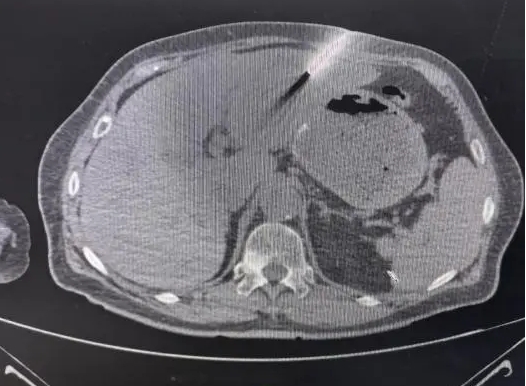

CT引导下经皮肝穿刺活检术:

精准采样,诊断保障

肝穿刺活检术是在影像引导下,通过细针穿刺获取病变组织进行病理学分析的微创操作技术。CT引导下经皮肝穿刺活检术凭借精准的成像定位,可实现全程操作精准性。术前,医生根据CT影像分析锁定胰头区和肝脏多发占位病灶位置,并详细评估病灶周围解剖结构;术中,通过CT实时定位,使穿刺针通过肋间间隙到达肿瘤区域。最终,可在避免邻近重要血管与胆管损伤的前提下,精准将穿刺针引导至目标病灶,顺利获取病理组织样本。术后,患者无明显不适,病理结果明确,为后续治疗方案制定提供了科学依据,展现出微创诊疗的高效与安全。

CT引导下肝穿刺影像图片。